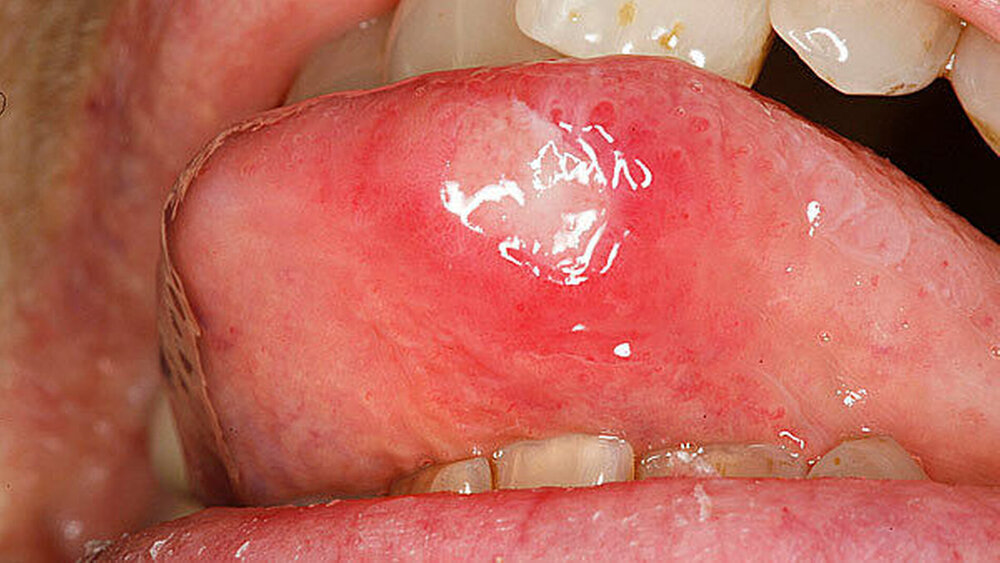

Übersicht 2 stellt die klinisch-morphologischen Erscheinungsformen der rekurrierenden Aphthose zusammen: Die Phasen der oralen und pharyngealen Aphthose sind gekennzeichnet durch ein bis zu 24-stündiges Prodromalstadium mit Kribbeln, Spannungsgefühl, Brennen, Rauigkeit, an das sich eine bis zu drei Tage dauernde präulzeröse Phase mit einem inflammatorischen Erythem beziehungsweise dem Auftreten einer indurierten Papel anschließt. Das darauf folgende ein bis 16 Tage dauernde ulzerative Stadium ist durch die typische fibrinbelegte Ulzeration mit aufgeworfenem Rand gekennzeichnet. Die sich daran anschließende Abheilungsphase kann vier bis 30 Tage andauern.